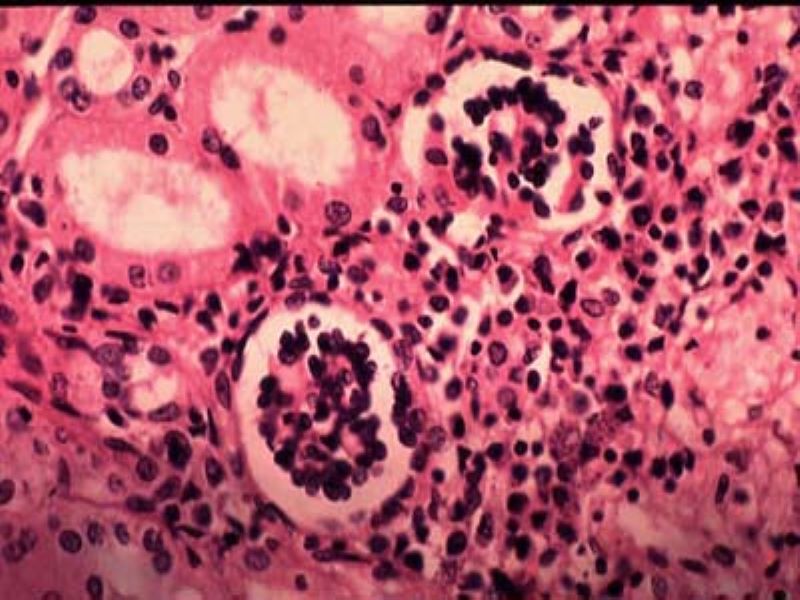

Kala azar or leishmaniases is one of the most dangerous neglected tropical diseases (NTDs) which is endemic in 76 countries, with approximately 200 million people at risk of infection, according to DoctorsWithoutBorders.org (DWB).

According to World Health Organization (WHO), Leishmania parasites are transmitted through the bites of infected female phlebotomine sandflies, which feed on blood to produce eggs.

Around 70 animal species, including humans, have been found as natural reservoir hosts of Leishmania parasites.